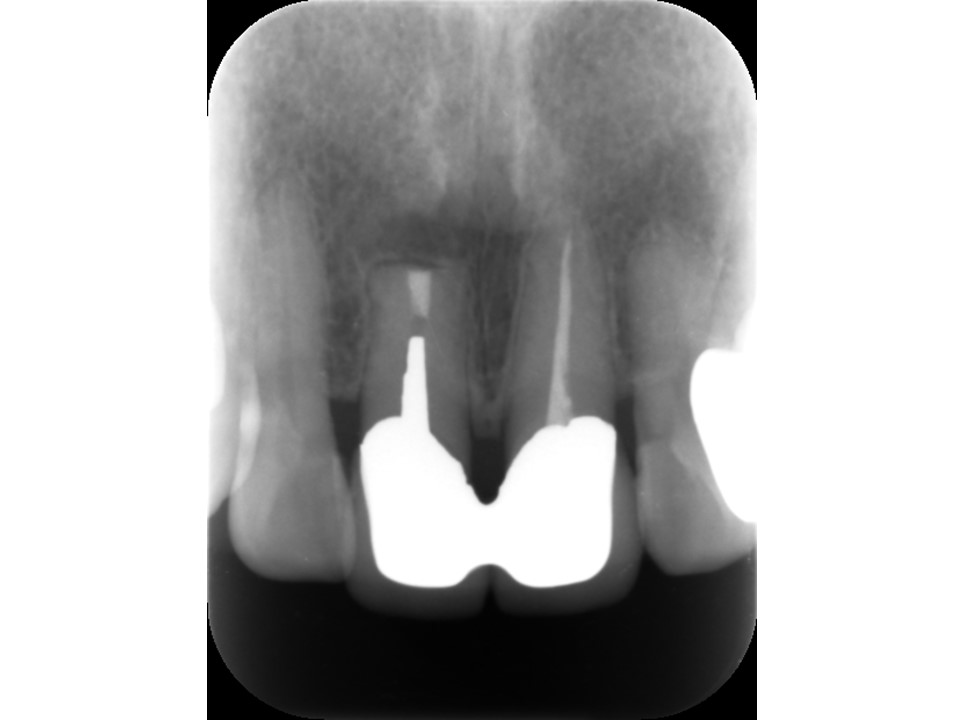

初診時レントゲン。上顎左側中前歯の激痛を訴えて来院。患者が痛む歯を特定しているにも関わらず異常なしと診断された。視診にて、上顎左側中切歯には大きなコンポジットレジンが充填してあり、これが原因と推察された。レントゲン上では、歯髄腔に近接するコンポジットレジン充填がされており、根尖部には黒く大きなレントゲン透過像を認めた。歯周ポケットはないものの、打診にて強い痛みを訴えた。総合的に判断して歯髄壊死から生じた急性化膿性根尖性歯周炎(根尖病巣)と診断し、根管治療が必要と判断した。